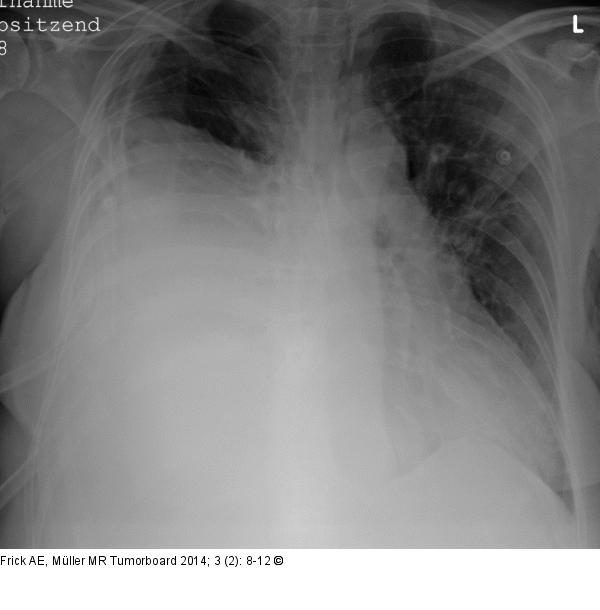

Abbildung 1: Biphasisches Synovialsarkom Präoperative Röntgenübersichtsaufnahme des Thorax: subtotale Verschattung des rechten Hemithorax. |

Präoperative Röntgenübersichtsaufnahme des Thorax: subtotale Verschattung des rechten Hemithorax. |